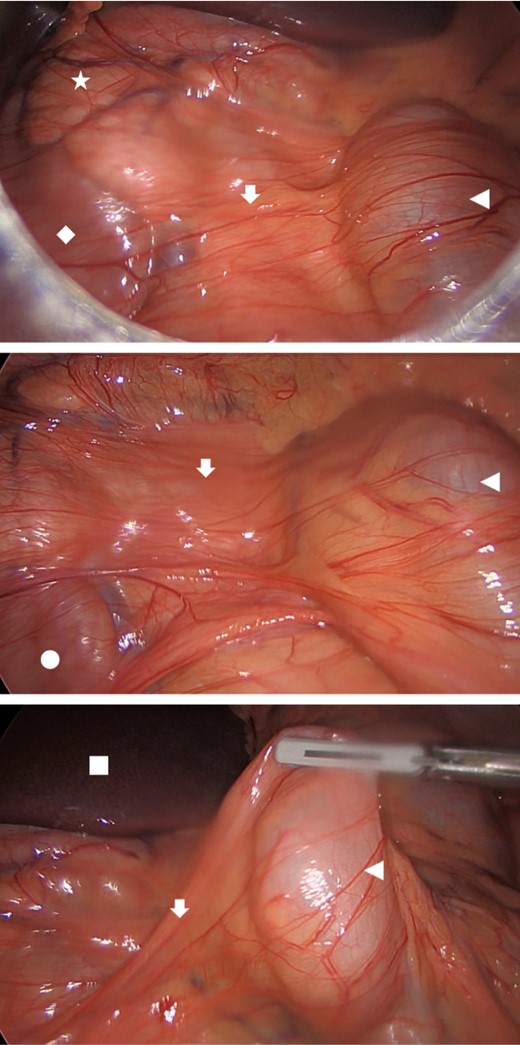

After obtaining an informed consent, the patient proceeded to an elective laparoscopic Ladd’s procedure. Intra-operative findings demonstrated partial malrotation of the intestine, multiple small bowel adhesions to the mesentery, Ladd’s bands running from the right upper quadrant and the lateral aspect of the second part of the duodenum to the caecum and ascending colon, and a caecum positioned towards the epigastrium and the left iliac fossa with adhesions to the sigmoid colon, splenic and hepatic flexures (Fig. 2). The Ladd’s bands were divided, and the terminal ileum, caecum and ascending colon were mobilized off the duodenum. Adhesions to the small bowel and between the colonic flexures, sigmoid and caecum were divided, thereby widening the mesentery. At the end of the procedure, the small and large bowels were placed in a non-rotated position.

Intra-operative findings demonstrating Ladd’s bands (arrow) attached to the caecum (arrowhead) and spanning across the head of pancreas (star), second (diamond) and third (circle) part of the duodenum; left lobe of the liver (square) in the background.